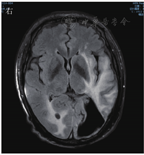

患者男,63岁,因"间断发热1年"于2020年6月29日入河南大学人民医院。患者1年前无明显诱因下出现发热,体温最高达38.0 ℃,伴有反应迟钝、吞咽困难、饮水呛咳、颈部硬肿,无咳嗽、咳痰,无胸闷、呼吸困难。患者于外院查血常规示感染相关指标高,CT检查示颅内感染可能(具体不详),予"美罗培南、万古霉素"抗感染治疗,体温可降至正常,但很快反复;后多次因"颅内感染"住院,予抗感染治疗,疗效差。4月余前因颅内高压、脑积水于外院行脑室-腹腔分流术。3月21日外院头颅MRI检查示左侧枕部颅板下积液、左侧颞枕顶叶明显水肿,增强后明显强化;颅脑术后改变。5月21日肺部CT检查示双肺多发结节影、条索影,考虑慢性炎症。为求进一步诊治来河南大学人民医院,门诊以"发热待查:颅内感染?脑室-腹腔分流术后"收入感染科。患者自发病来,神志欠清,精神差,食欲及睡眠可,二便正常,体质量较前无明显减轻。既往史:2003年因颈椎破坏行植骨术;2013年因"发热伴头痛"发现颅内病变,曾就诊于多家医院均未明确诊断,病情缓慢进展;2018年因"头痛加重"行颅内病变切除术,术后考虑感染性病变,间断抗感染治疗,病情仍无改善。体格检查:体温为36.8 ℃,脉搏为88次/min,呼吸为20次/min,血压为135/85 mmHg(1 mmHg=0.133 kPa)。神志欠清,反应迟钝,对答欠切题,计算力下降。双侧额纹变浅,闭目力差,双侧鼓腮力、咀嚼力差;伸舌困难,舌不能完全伸出;双侧瞳孔等大等圆,眼球活动度差,尤其上视、右视时明显,对光反射迟钝,视力下降;颈部红肿、僵硬,无压痛;双肺听诊呼吸音清,未闻及干、湿啰音;心前区无隆起,心界不大,律齐,各瓣膜听诊区未闻及心脏杂音及心包摩擦音;腹部平软,无压痛,肝脾肋下未及,移动性浊音阴性,肠鸣音正常;双下肢无水肿,肌力3级,腱反射(-),病理征(+)。考虑为免疫性疾病,予补液、营养支持等对症治疗。实验室检查:IgG为37 910 mg/L,抗髓过氧化物酶抗体为24.21 RU/mL,IgE为208.3 IU/mL,IgG4为10 400 mg/L;IL-6为115.88 ng/L;ESR为106 mm/1 h;CRP为146.36 mg/L;降钙素原为0.12 μg/L;血常规、尿常规、粪便常规、游离三碘甲腺原氨酸、游离甲状腺素、促甲状腺激素、T.SPOT.TB检测、β-D-葡聚糖试验、半乳甘露聚糖抗原试验、EB病毒DNA、CMV DNA、布鲁菌抗体、肿瘤标志物均阴性。6月30日胸部CT检查示双肺多发结节,见图1。7月2日头颅MRI平扫+增强检查示脑内多发异常信号影;后纵裂池处脑膜、小脑幕及左侧颞部硬脑膜增厚并明显强化;左侧枕叶局部脑穿通畸形形成,见图2。进一步行腰椎穿刺脑脊液检查示单核细胞计数为66×106/L,蛋白质为6.02 g/L,葡萄糖为2.02 mmol/L,氯化物为119.9 mmol/L。考虑为IgG4相关疾病(immunoglobulin-G4 related disease,IgG4-RD)。7月2日请病理科会诊外院术中脑组织病理切片,结果示(左枕)纤维组织增生伴玻璃样变性,局部胶原化,淋巴袖套结构可见,血管周围及硬化间质内见较多淋巴细胞及浆细胞浸润,浆细胞形态成熟,见图3;免疫组织化学染色示纤维及血管周边可见多量IgG4+浆细胞浸润,IgG4+浆细胞约为50~100个/高倍视野,见图4。根据患者检查结果和多科室专家会诊,诊断为IgG4-RD,累及中枢、肺部、皮肤、骨骼。由于患者病变侵犯脑干,有脑水肿、颅内压升高等表现,可能出现呼吸、心跳骤停等严重并发症,与患者家属沟通患者病情。7月10日开始予甲泼尼龙(500 mg,1次/d,静脉滴注)冲击联合丙种球蛋白(20 g,1次/d,静脉滴注)治疗。当天患者眼球转动基本正常,进食无呛咳,意识、反应和言语明显好转,颈部硬肿好转。予静脉滴注甲泼尼龙500 mg 3 d、240 mg 3 d、120 mg 3 d、80 mg 3 d、40 mg 3 d,以及静脉滴注丙种球蛋白20 g (1次/d) 5 d,患者症状明显改善,复查IgG、IgG4、ESR、CRP均较前下降。7月13日肺部CT检查示双肺结节明显缩小,见图5。7月19日头颅MRI检查示颅内局部脑水肿减轻,后纵裂池处脑膜、小脑幕及左侧颞部硬脑膜病变缩小,见图6。患者症状逐渐好转,7月24日患者及家属要求出院。出院后继续予甲泼尼龙治疗,后联合吗替麦考酚酯,患者一般情况稳定,定向力、记忆力、认知力正常,言语流利。